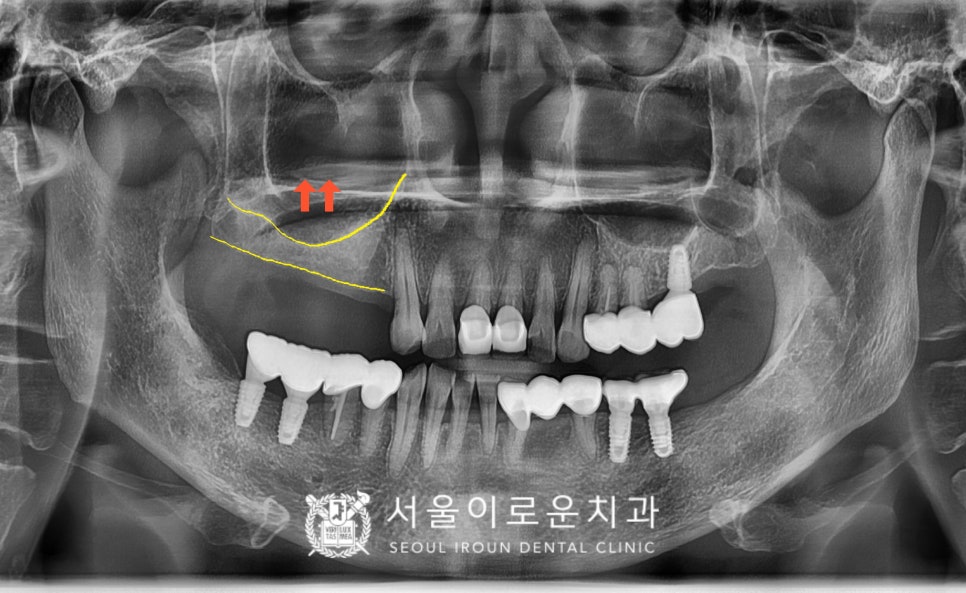

정밀한 검사를 위해

파노라마 사진을 촬영해 보았더니

위턱의 오른쪽 첫 번째 작은 어금니(#14)부터

두 번째 큰 어금니(#17)까지

모두 4개의 어금니가 상실된 상태였는데요.

그리고 위턱 왼쪽 어금니 자리에

상악동막이 내려와 있어

잔존 뼈와 상악동까지의

수직적인 뼈의 양이 부족하여

상악동 거상술 중

치조정 접근법을 활용하여

임플란트 식립을 진행하기로 하였는데요.